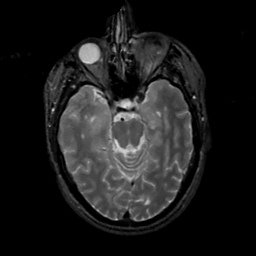

MR Study #2, February 17, 1991 -- Slice #18

[Home][Help][Clinical][Tour 1][Tour 2] Slice 18